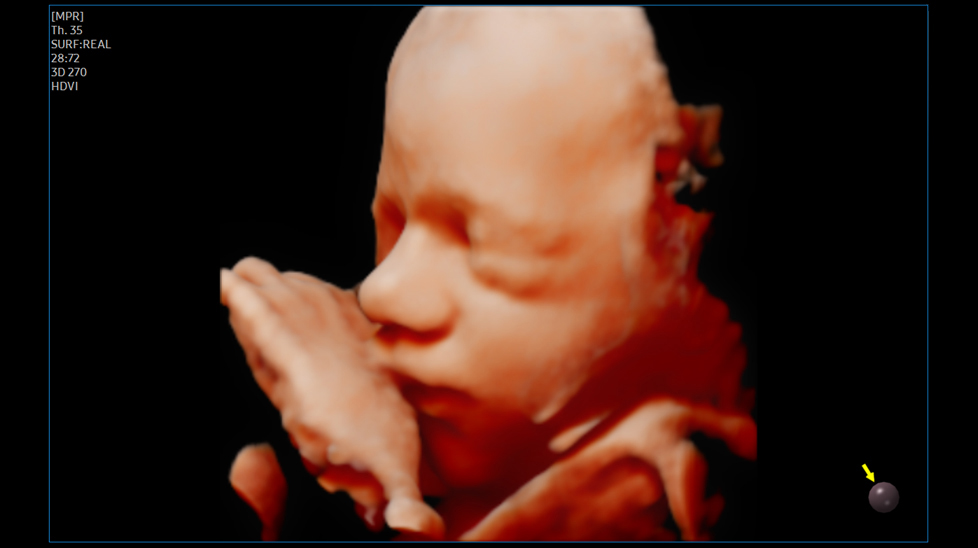

Реалистичное описание характеристик 3D / 4D

CrystalLiveTM в формате 3D / 4D обеспечивает пользователям более реалистичные изображения с высоким разрешением. Она превосходит традиционные технологии 3D-визуализации в плане просмотра мелких деталей и световых эффектов.

Реалистичное отображение 3D-анатомии RealisticVue™ отображает 3D-анатомию в высоком разрешении с исключительной детализацией и реалистичным восприятием глубины. Выбираемое пользователем направление источника света создает затейливо градуированные тени для более четких анатомических структур.TM

на изображении: Ранний зародыш с помощью RealisticVueTM

Объемное изображение высокой четкости HDVITM - это технология объемной визуализации, которая улучшает визуализацию краев и небольших структур на объемных данных. Улучшенная выразительность границ и насыщенность изображения позволяют передать самые детали от угла до тени плода.

на изображении: Позвоночник плода с 3D